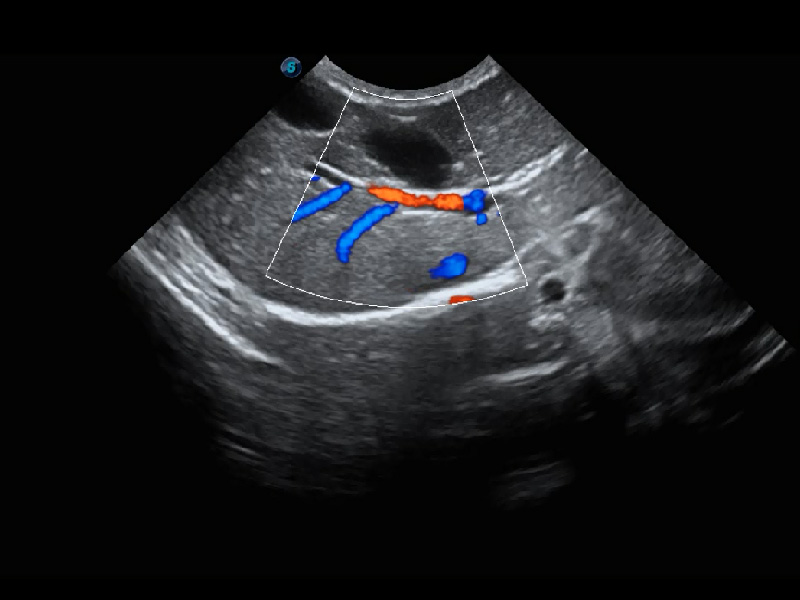

ProPet 60 作为一款高端台式动物超声设备,为动物医生的日常诊断提供了一系列贴合动物临床需求、解决临床实际问题的高级成像功能。凭借全系列高清探头,满足医生对腹部、心脏、生殖、浅表、肌骨等成像的所有需求,切实帮助您提升检查效率,提高诊断信心。